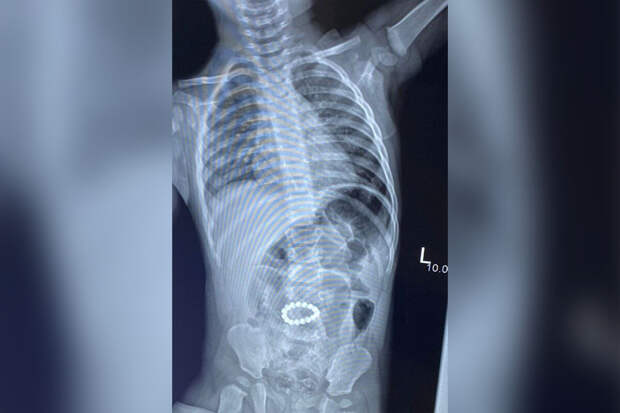

Ребенка привезли в больницу с жалобами на слабость, вялость, отсутствие аппетита и стула. Во время обследования врачи нашли в брюшной полости пациента 6 магнитов, которые соединились в кольцо.

Выяснилось, что с момента игры с магнитами до времени госпитализации прошло двое суток."Магниты спаяли петли кишечника, вызвали некроз и через перфорации вышли в брюшную полость, вызывая признаки перитонита", - рассказал детский хирург Илья Акишкин.